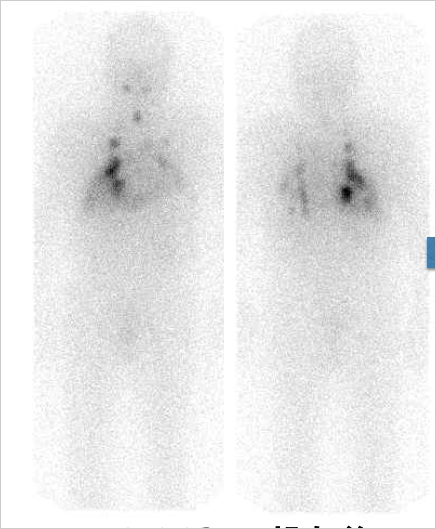

治療病室を退室退院後1週間を目処に外来受診していただき、I-131シンチ撮像を行います。以下は、典型的な肺転移のI-131シンチです。(図3)肺転移にI-131が多く取り込まれており、そのような場合は、治療効果が期待できるので2回目、3回目のI-131治療を追加実施することもあります。